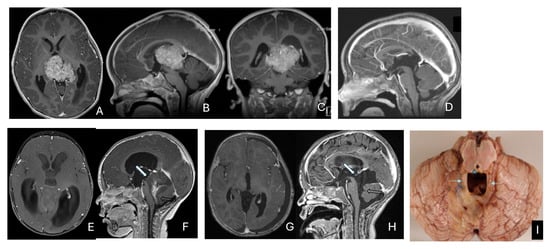

Histogenesis of Atypical Teratoid Rhabdoid Tumors: Anatomical and Embryological Perspectives

Objectives: Atypical teratoid/rhabdoid tumors (ATRTs) are rare, malignant central nervous system (CNS) neoplasms that predominantly affect infants and young children. While ATRT arises throughout the CNS, its extracranial counterpart, malignant rhabdoid tumor, occurs in other organs. A single-institutional cohort is reviewed to map anatomic distribution of pediatric ATRTs and to integrate a literature review to contextualize ATRT histogenesis from anatomical and embryological perspectives. Methods: A retrospective review was conducted on a cohort of 50 pediatric patients with ATRT treated over 20 years. Demographic, surgical, and neuroimaging data were correlated to define tumor location, extent, and compartmental involvement. A focused literature review synthesized molecular subclassifications and proposed cells of origin/cytogenesis. Results: Of the 50 ATRTs, 18 (36%) were infratentorial, 15 (30%) supratentorial, 11 (22%) in the pineal region, and 6 (12%) in the spinal compartment. Among infratentorial tumors, 10 were centered in the fourth ventricle, with or without extension into the cerebellopontine angle (CPA) cistern; the remainder arose in the CPA. Among ATRTs of the cerebral hemispheres, 3 showed bi-hemispheric involvement crossing the falx cerebri. ATRTs of the pineal region predominantly originated from the superior medullary velum. These topographic data were corelated with embryological and molecular information available in the literature. Conclusions: ATRTs arise across diverse neuroanatomical compartments—including intraparenchymal, intraventricular, extra-axial, and extradural sites—underscoring biological heterogeneity. Inactivation of SMARCB1 is the defining molecular event and principal oncogenic driver, although the upstream mechanisms precipitating these alterations remain incompletely resolved. Molecular subgroups—ATRT-TYR, ATRT-SHH, and ATRT-MYC—display distinct age distributions and anatomic predilections, implicating developmental context in tumor initiation. The characteristic cellular admixture of rhabdoid cells with mesenchymal and/or epithelial differentiation, together with intra- and extra-axial and occasional extradural presentations, supports a model in which at least a subset of ATRTs may originate from neural crest-derived lineages, despite little or no neural crest contribution to brain parenchyma development. Neural plate border progenitors with bipotent features represent a plausible intraparenchymal cell of origin. Definitive resolution of these origins and the mechanisms of SMARCB1 disruption will require integrated approaches. Further investigations are warranted to clarify these mechanisms.